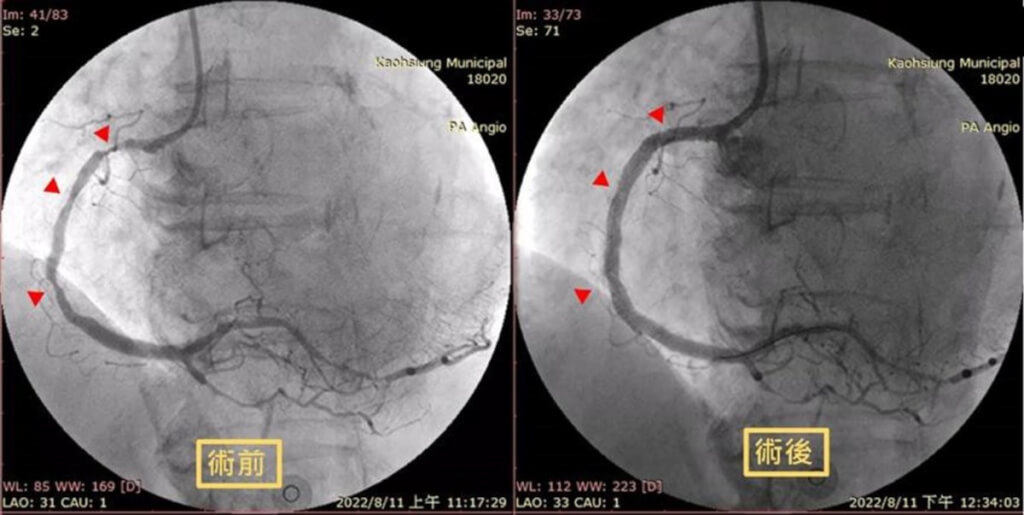

团队随即启动紧急心导管并放置金属涂药支架,打通阻塞的右冠状动脉,并经过加护病房住院调养后,使情况稳定,如今已准备出院。